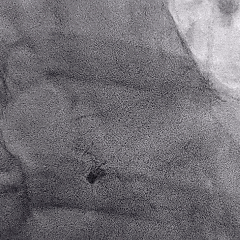

Lefort封堵器释放

封堵器释放前造影

下缘未露肩

符合Lefort释放原则,释放后造影,封堵器形态良好,未发生移动